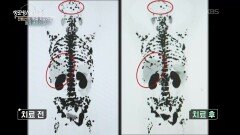

재생09:14생로병사의 비밀고령 환자의 희망 - 표적치료제 | KBS 260422 방송

재생11:43생로병사의 비밀조혈모세포 이식 후 또 다른 싸움 - 이식편대숙주질환 | KBS 260422 방송